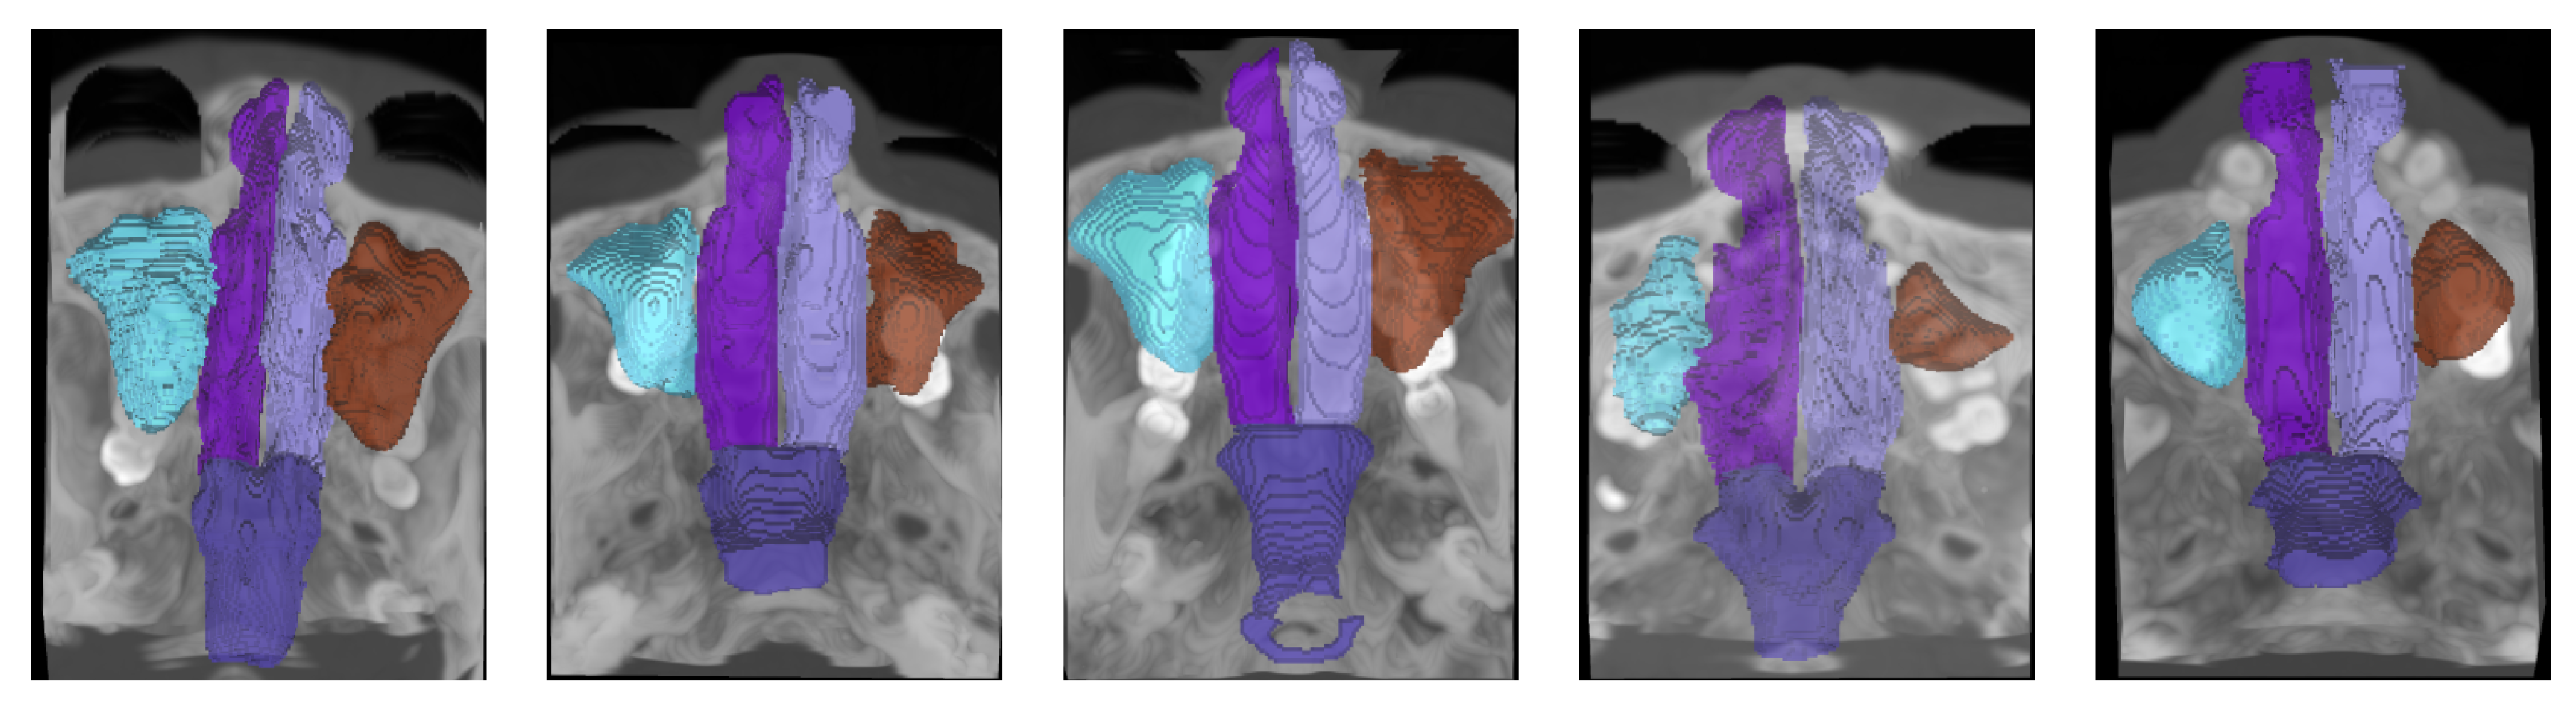

Each scan is accompanied by meticulous, pixel-wise annotations of five anatomical structures: the left nasal cavity, right nasal cavity, nasal pharynx, left maxillary sinus, and right maxillary sinus. These annotations were initially performed by skilled annotators and subsequently refined and verified by senior experts to ensure high accuracy and consistency. Furthermore, the dataset is organized into five pre-defined folds to support cross-validation and robust benchmarking of segmentation algorithms.

We report samples of the NasalSeg dataset along with over-imposed annotations in Figure 1

Figure 1. Samples from the NasalSeg dataset along with corresponding labels.